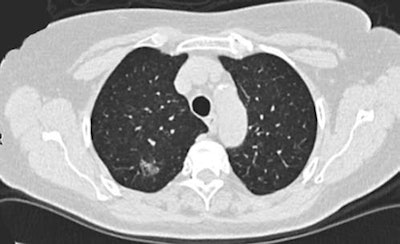

CT lung cancer screening is at the fore with 10 new recommendations from the European Society of Thoracic Surgery (ESTS). A recently published paper written by an international team of eight experts in the field of thoracic surgery outlines the ESTS's plans for improving lung cancer CT screening by involving surgeons at all levels of screening strategy.

According to the paper, around 269,000 deaths in Europe from lung cancer were expected in 2016. The authors believe it is clear that screening and early detection can contribute to reducing lung cancer mortality. They also pointed to CT screening being recommended in a white paper by the European Society of Radiology (ESR) and the European Respiratory Society (ERS).

"With the increasing rate of detection of early lung cancer through screening [low-dose CT] LDCTs, surgeons will be called to provide the necessary expertise to obtain both diagnosis and treatment of screen-detected nodules," the authors stated.